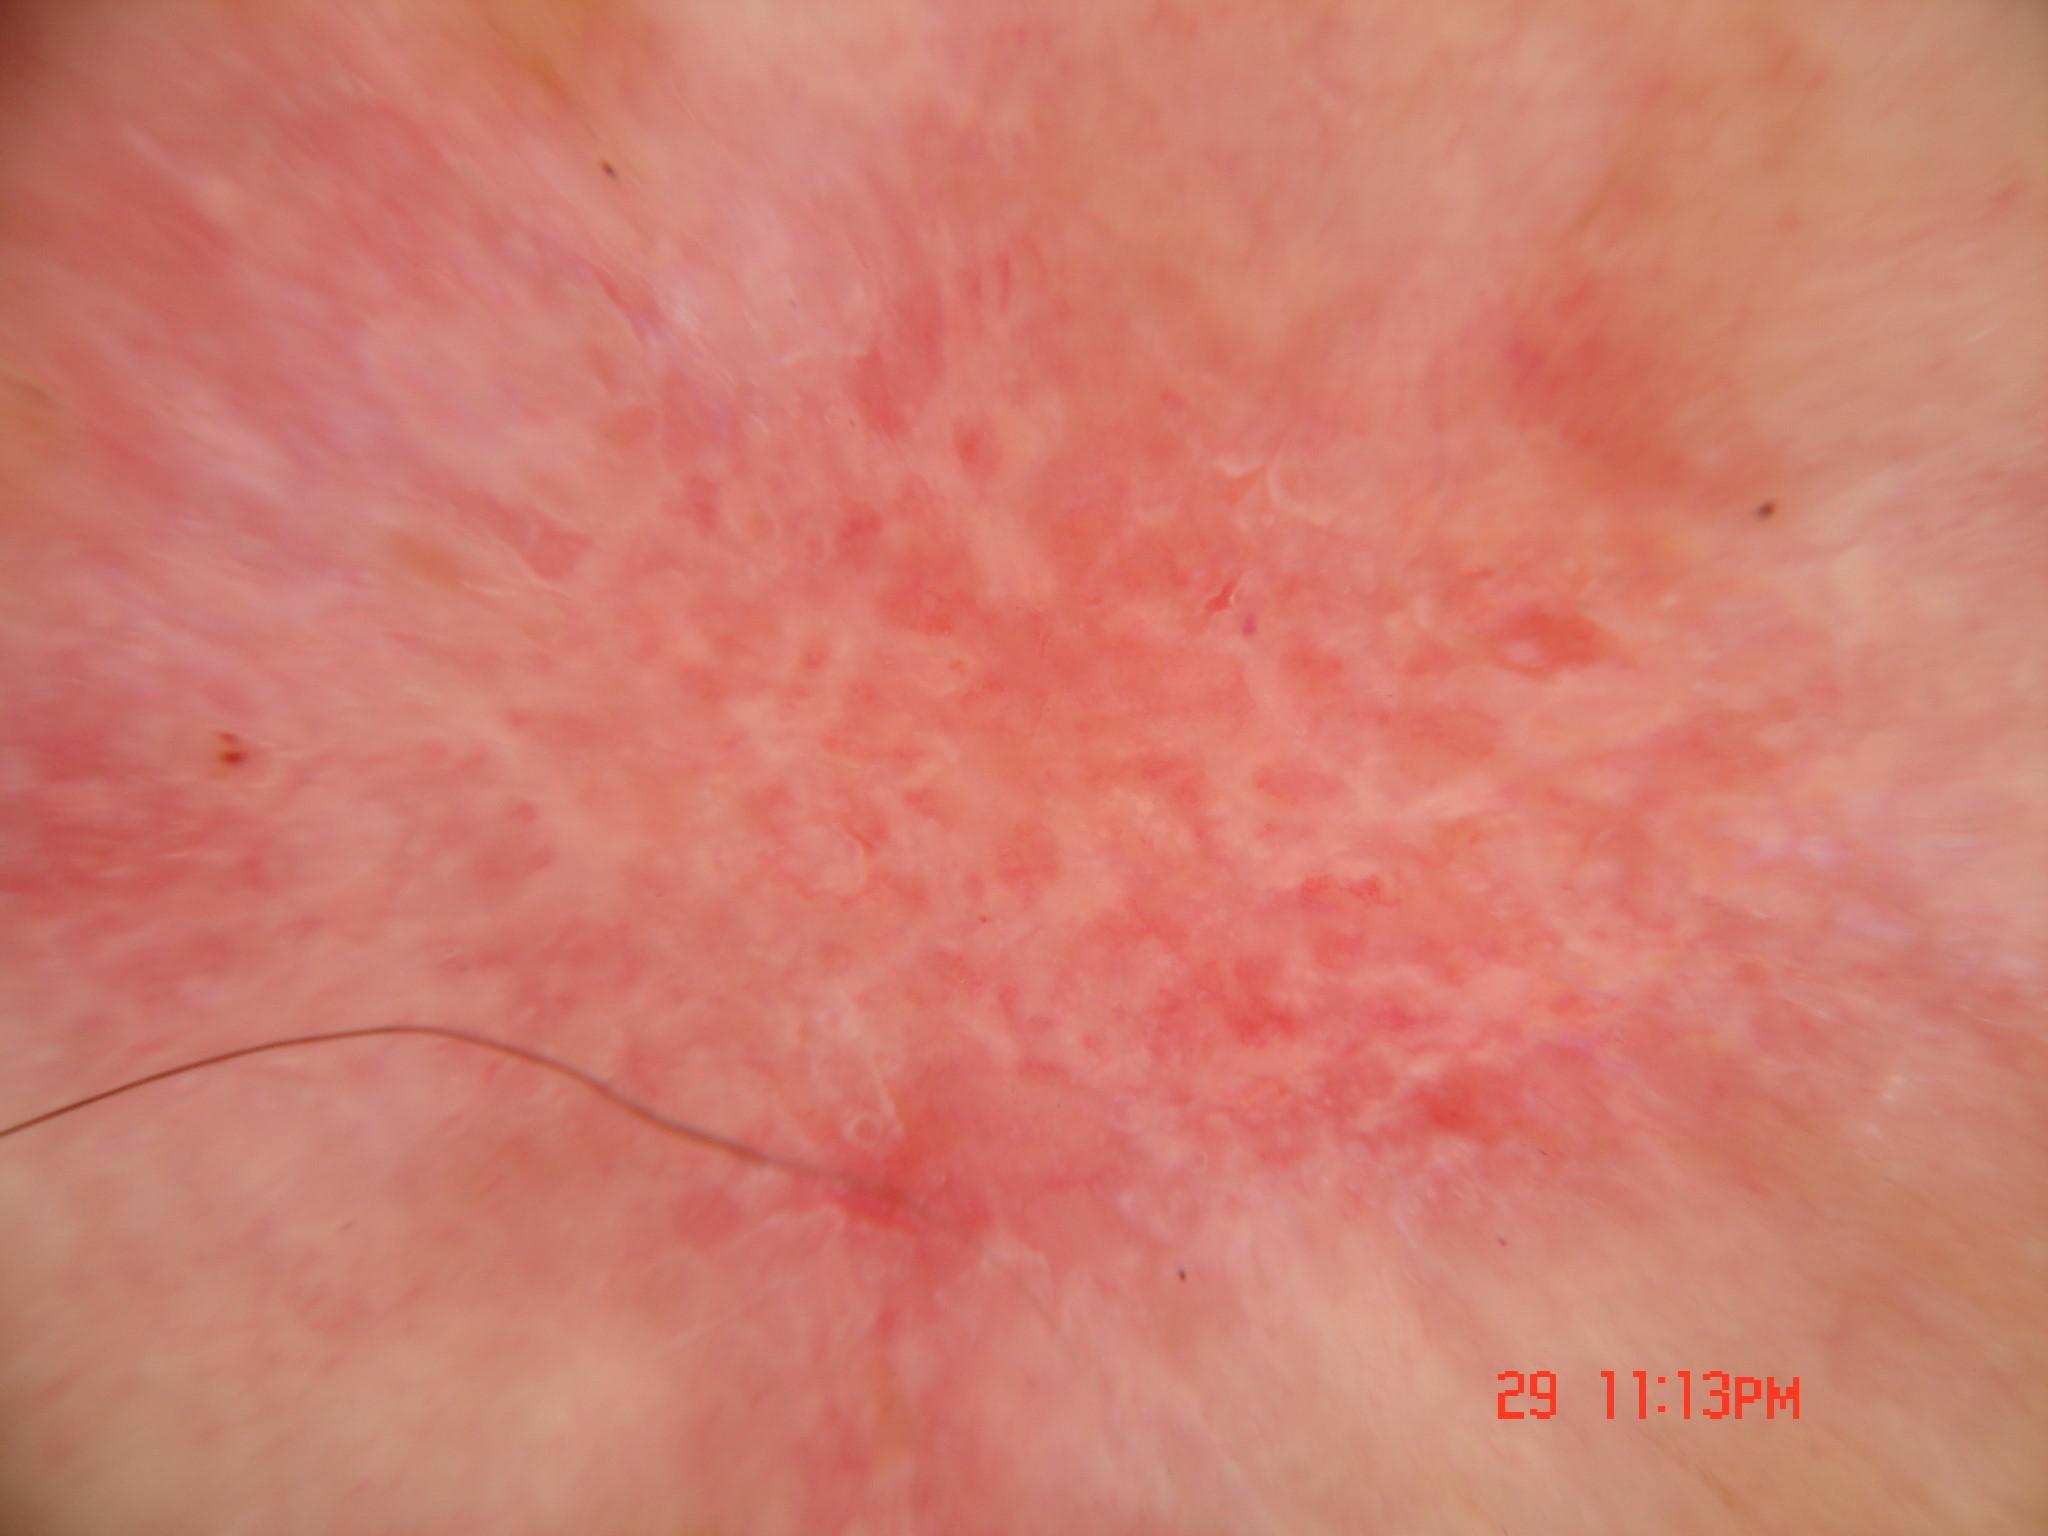

{

"age_approx": 60,

"anatom_site_general": "head/neck",

"concomitant_biopsy": true,

"dermoscopic_type": "contact non-polarized",

"diagnosis_1": "Indeterminate",

"diagnosis_2": "Indeterminate epidermal proliferations",

"diagnosis_3": "Solar or actinic keratosis",

"diagnosis_confirm_type": "histopathology",

"family_hx_mm": false,

"image_type": "dermoscopic",

"melanocytic": false,

"patient_id": "IP_1677655",

"personal_hx_mm": false,

"sex": "female"

}